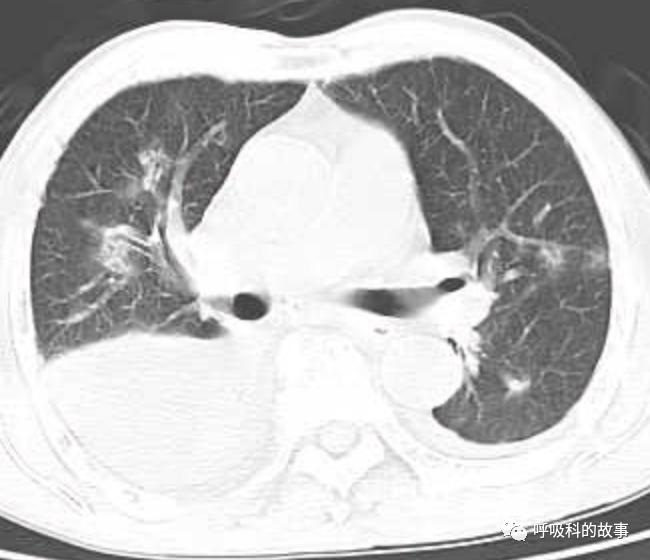

接着,我打开电脑看病历:患者,男,68岁,主诉:发热、头痛伴乏力10余天,咳嗽4天。肺部CT一看是右下叶大片实变肺炎,双侧少量胸腔积液,两上肺内中带片絮状斑片状影。2020.11.30 在外院检查 PCT 7.42ng/ml,ALT 199U/L,AST 250U/L,白蛋白24.7g/L,CRP 108.7mg/L,乳酸脱氢酶LDH388U/L(正常50-240),钾3.27mmol/L;血常规:白细胞4.9*10^9/L,中性85.2%。在外院给予了亚胺培南2天和本院美罗培南治疗2天后,效果并不理想。

(6)肺部影像以大叶性肺炎为主,其他部分是合并肺水肿的影像;